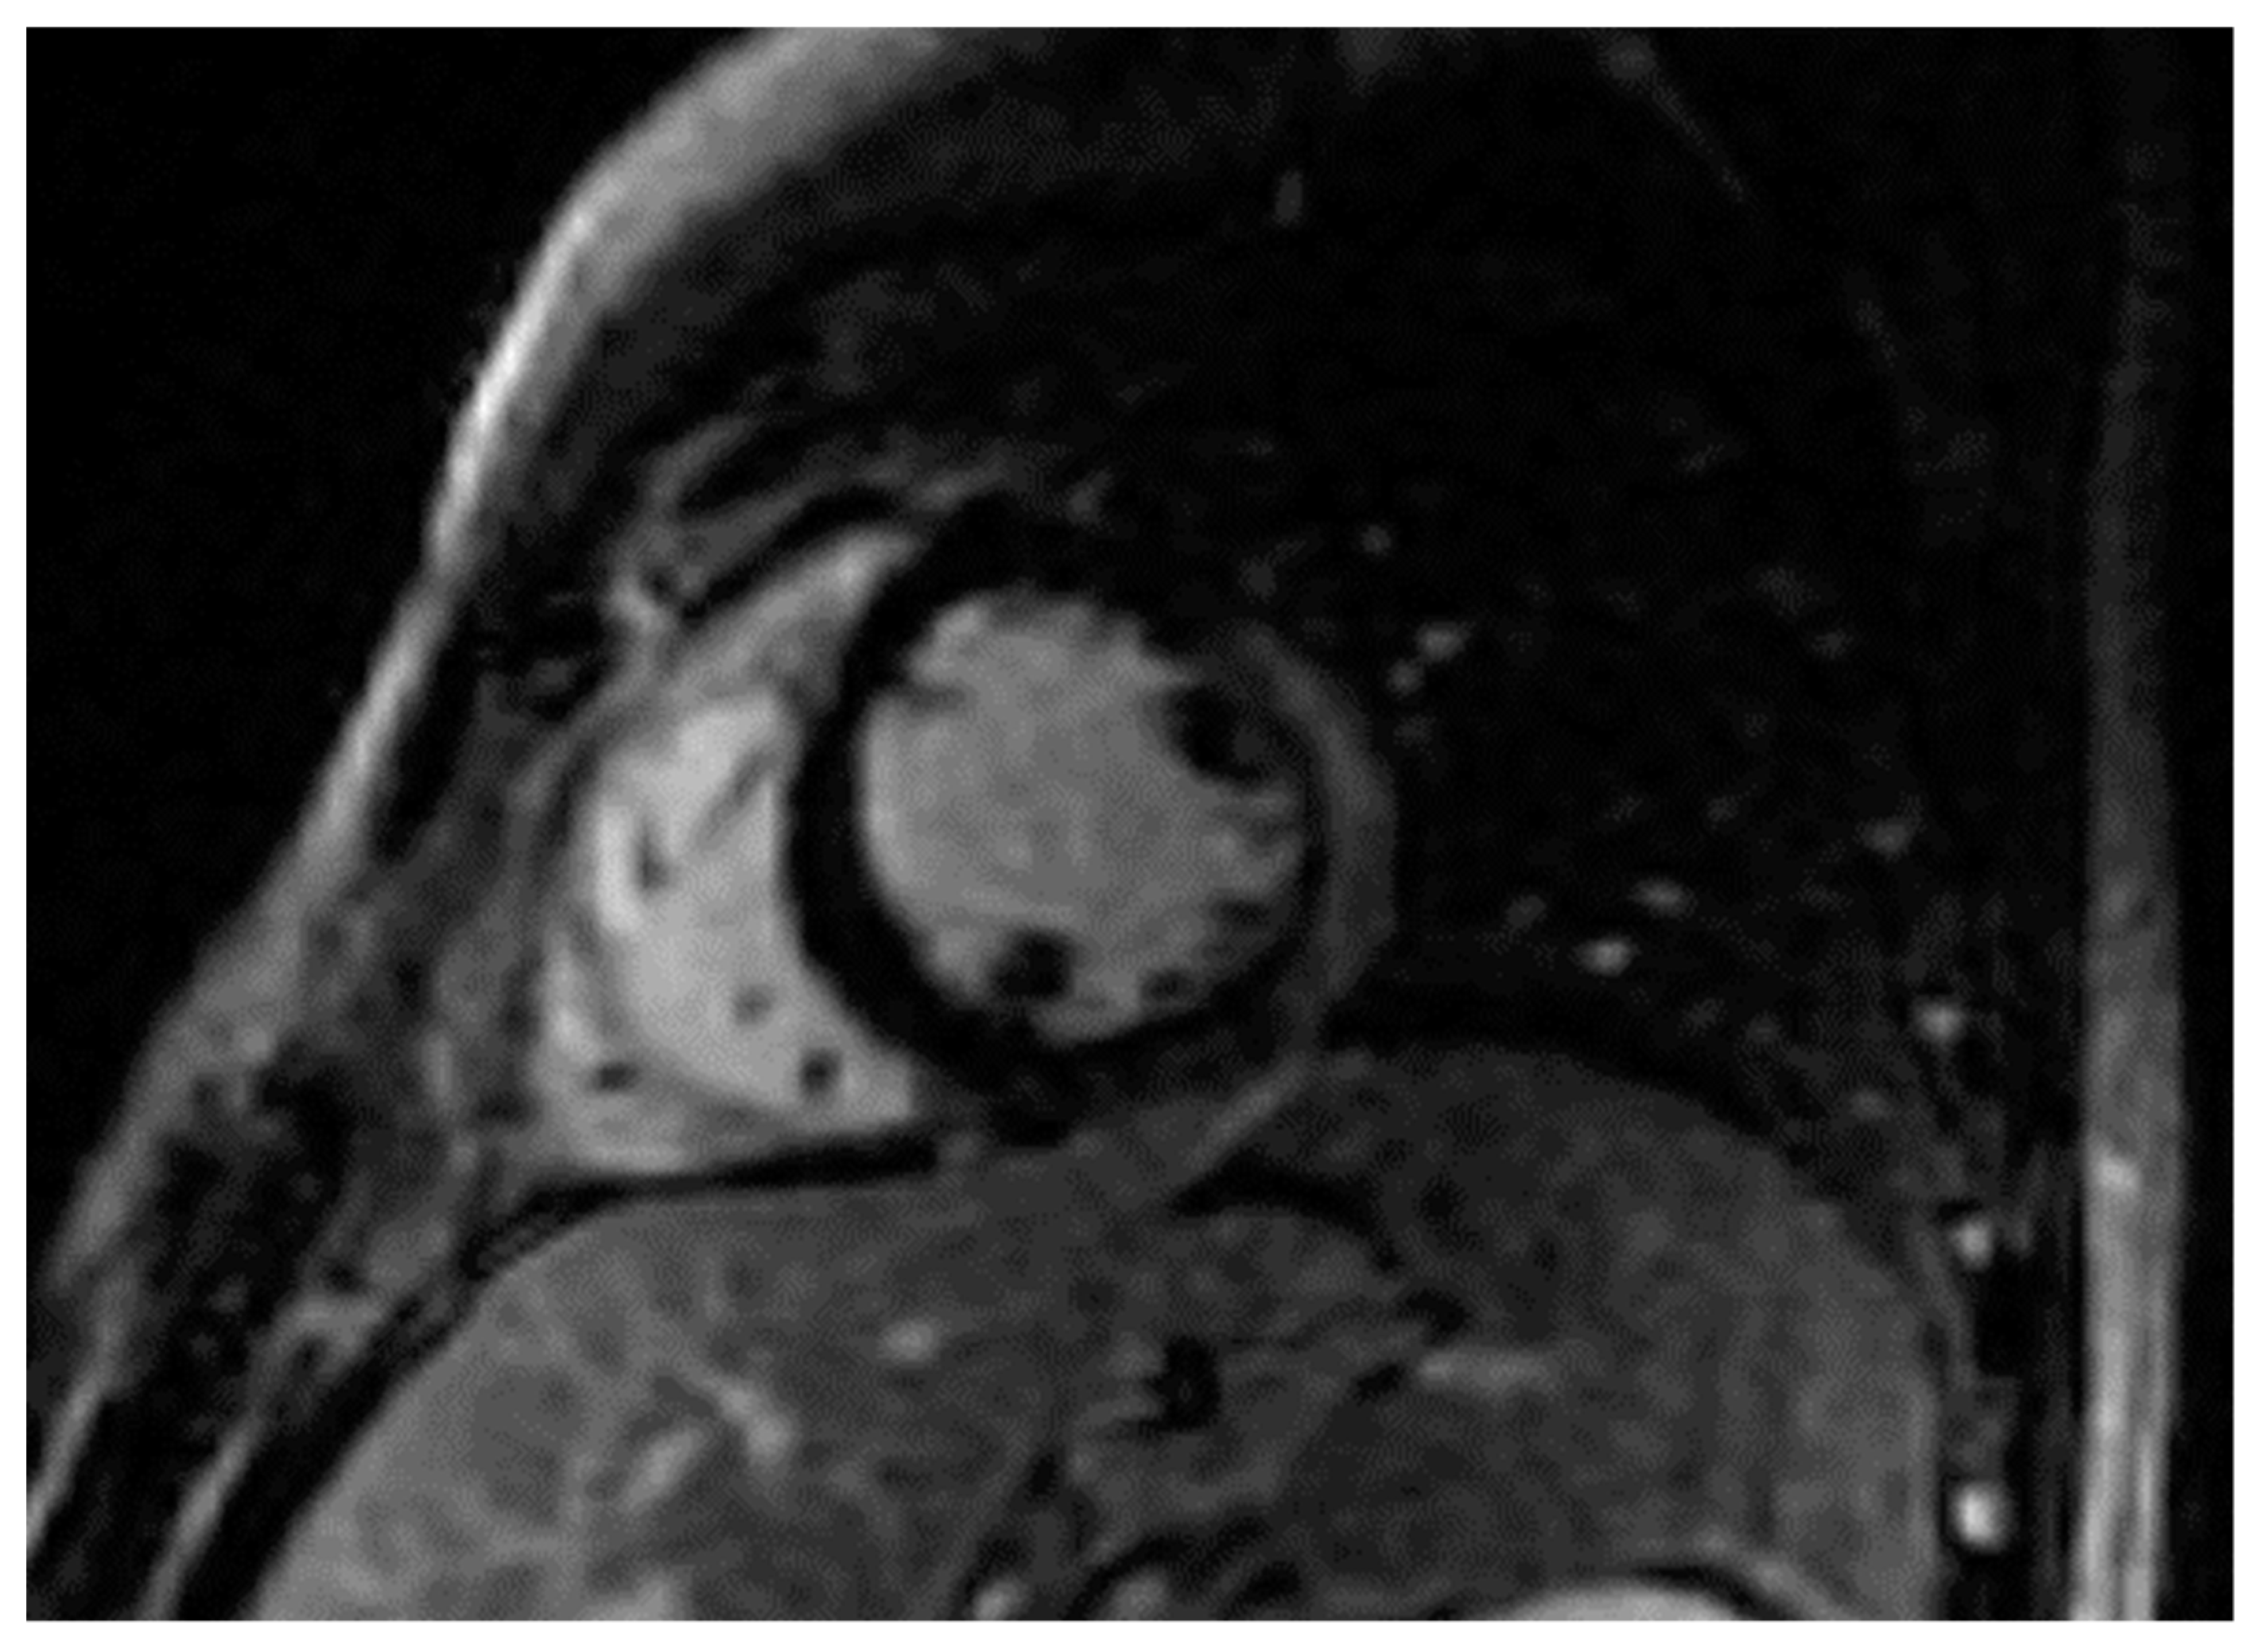

Figure 2.

Short axis LGE image showing subepicardial fibrosis (bright area) in the lateral wall of LV of the same patient.